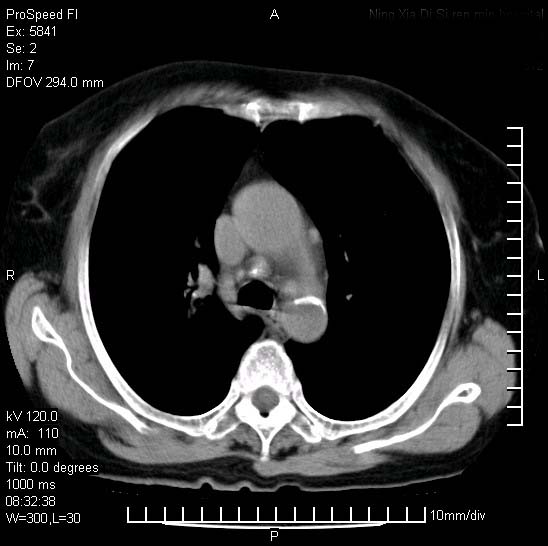

胸痛,咳嗽,气短一周,无发热。右上肺见一结节灶,边缘刺角,内见多个小钙化结节。考虑结核球?肿瘤? 余无异常没有上传。

考虑右肺上叶继发性肺结核,结核球形成。

考虑结核球,并胸膜局限性增厚!!